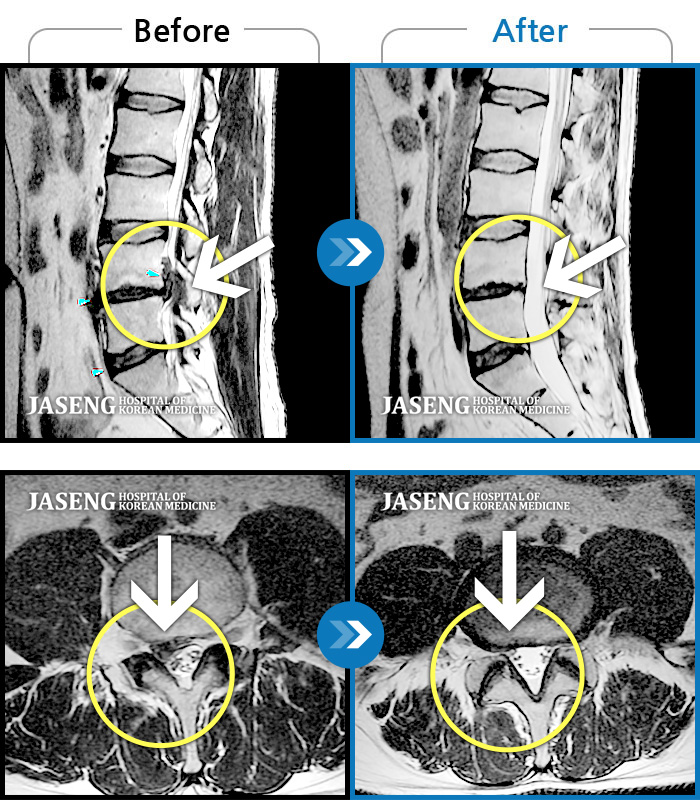

허리디스크

보라매 · 강준규 원장

우측 허리부터 엉치까지 아프고, 다리 저림이 지속적으로 심하게 느껴져요.

촬영시기

2024.04.06 ~ 2025.02.22

우측 엉치 부터 발 끝까지 저리고 아픈 증상이 있었다.

2019.02.28 ~ 2020.02.10